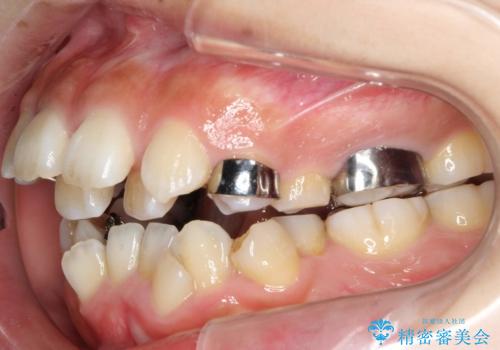

- 治療計画

- 上顎の骨格性拡大+両側第1小臼歯抜歯 によりスペースを獲得、フルリンガルによるワイヤー矯正を計画した。